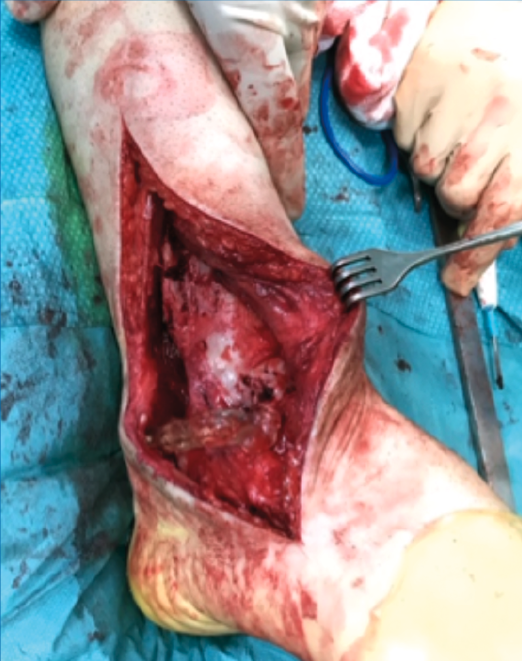

Figura 4. Tallado intraoperatorio con ayuda de la guía 3D.

- Tallado del injerto de manera intraoperatoria (Figuras 4 y 5).